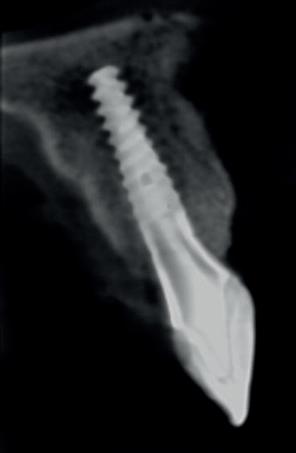

De implantaatplaatsing en de beslissende fout (afbeelding 1-13)

De extractie verliep voorspoedig, waarbij ik zoals al-

primaire stabiliteit van 60 Ncm.

11. Röntgenfoto ter controle van de plaatsing en de angulaire. Dit bone-level implantaat werd 4 mm onder de weke delen geplaatst.

tijd probeerde de buccale botlamel intact te houden. Dit is cruciaal voor latere botbehoud en implantaatplaatsing. Na curettage en spoelen van de alveole beoordeelde ik de situatie opnieuw: de botcondities leken gunstig voor een immediaat implantaat.

Hier begon echter de cruciale fout in mijn klinisch besluitvormingsproces. In mijn streven naar maximale primaire stabiliteit - wetende dat immediaat belasten enkel mogelijk is bij hoge stabiliteit -on-

derprepareerde ik de osteotomie. Dit betekende dat ik een iets te smal implantaatbed creëerde, in de hoop dat het implantaat stevig in het bot verankerd zou worden.

Op papier leek dit een logische stap: het MegaGen AnyRidge-implantaat dat ik koos, gaf me een stabiliteit van 60Ncm—een cijfer dat vertrouwen gaf in immediaat belasten. Maar in mijn enthousiasme had ik onvoldoende rekening gehouden met de biologische gevolgen van overmatige compressie.